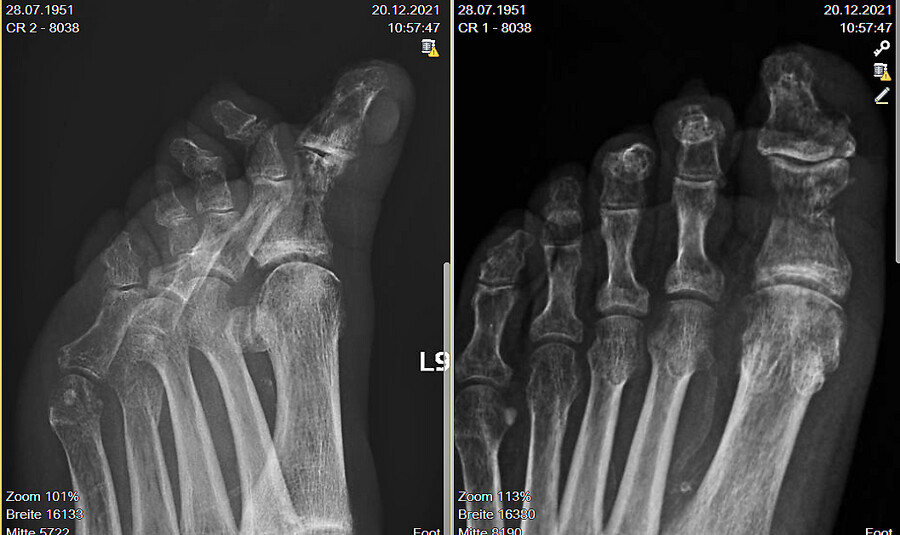

Röntgen linker Vorfuß in zwei Ebenen wenige Tage nach der Erstvorstellung (Abb. 12): Radiologisch sind deutlich die Osteolysen im Bereich des Grundgliedes und des Endgliedes DI links zu sehen. Im Einklang mit dem plantarem, tiefen Ulcusbefund und dem manifesten Infekt ist dies sicher als Osteomyelitis zu werten.